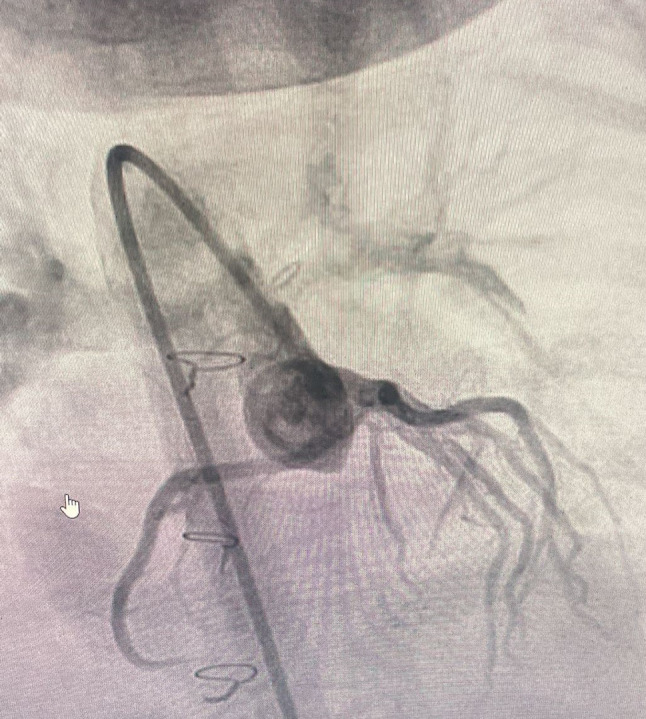

冠状动脉旁路移植术(CABG)在儿童心脏手术中是一种非常罕见的手术,主要是因为这一人群的冠状动脉疾病发病率低。然而,当有指示时,使用胸内动脉(ITA)作为移植物对于确保长期成功至关重要。本病例报告描述了一位冠状动脉异常的患者,右冠状动脉从左主冠状动脉出发,沿右心室流出道横贯。患者在Rastelli手术后出现晚期冠状动脉压迫,突出了ITA移植物在手术治疗中的关键作用。

Coronary artery bypass grafting (CABG) is an exceedingly rare procedure in pediatric cardiac surgery, primarily due to the low incidence of coronary artery disease in this population. However, when indicated, the use of the internal thoracic artery (ITA) as a graft is crucial for ensuring long-term success. This case report describes a patient with a coronary artery anomaly where the right coronary artery is taking its origin from the left main coronary artery and transversing along the right ventricle outflow tract. The patient experienced late coronary compression after Rastelli operation, highlighting the critical role of ITA grafts in the surgical treatment.